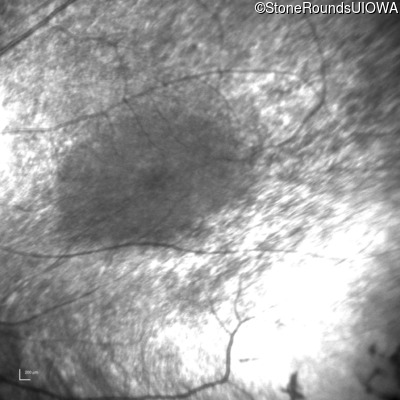

Infrared Fundus Photograph - Left - No Light Perception

Exemplar